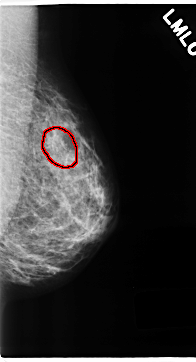

C_0199_1.LEFT_MLO

LEFT_MLO LINES 4704 PIXELS_PER_LINE 2536 BITS_PER_PIXEL 12 RESOLUTION 50 OVERLAY

FILE: C_0199_1.LEFT_MLO.OVERLAY

TOTAL_ABNORMALITIES 1

ABNORMALITY 1

LESION_TYPE CALCIFICATION TYPE PLEOMORPHIC DISTRIBUTION CLUSTERED

ASSESSMENT 5

SUBTLETY 4

PATHOLOGY MALIGNANT

TOTAL_OUTLINES 1

BOUNDARY